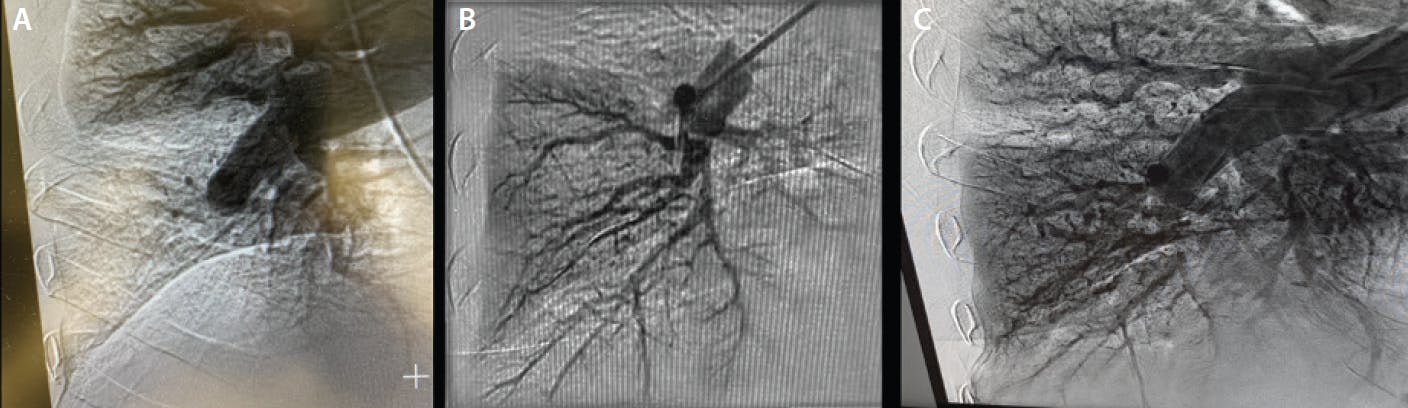

BPA uses standard angioplasty techniques to dilate obstructed pulmonary arteries, restoring blood flow to the lung and alveolar tissues. The therapeutic option of BPA as an adjunct to PH-targeted medical therapy has generated enthusiasm among many United States institutions to offer BPA as a part of their pulmonary arterial hypertension programs. Instead of removing the organized fibrotic clot as with PTE surgery, BPA reestablishes lung perfusion by creating a channel through organized thrombotic material via reducing vascular narrowing from chronic fibrotic lesions. Depending on the extent of BPA-treatable target lesions, there can be significant reduction in pulmonary vascular resistance (PVR) and RV afterload, leading to improved RV function and size. Additionally, BPA can improve pulmonary parenchymal perfusion by reducing dead space ventilation (Figure 1 and Figure 2).

Figure 1. Right pulmonary angiogram showing lower lobe artery occlusion in a patient with severe comorbidities (A). Angiogram post-BPA showing revascularization of the lower pulmonary artery (B). Angiogram post-BPA showing restoration of the alveolar perfusion of the lower lobe (C).